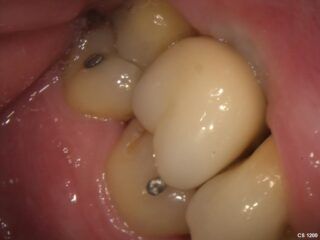

Once the implant is fully healed, a custom-made crown is placed on top. This crown looks and functions like a natural tooth, restoring your smile and bite.

If you have several missing teeth, implants can support a dental bridge. This is a secure, permanent solution that feels and looks like natural teeth.

Once healing is complete, a custom-made dental crown is fitted onto the implant. This restores both the function and natural look of the missing tooth.